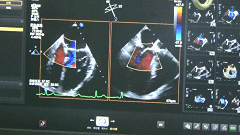

彩色超声多普勒缺认反流明显减少、夹合效果良好